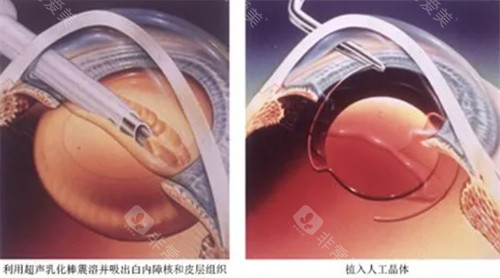

普瑞眼科在济南的口碑一直不错,尤其是其引进的德国蔡司三焦点晶体技术,能帮助老年人一次性解决白内障和老花眼问题。

三焦点晶体:相比传统单焦点,可同时优化远、中、近视力,术后不用戴老花镜。

个性化方案:根据患者角膜状况、用眼习惯定制手术,比如喜欢看书或开车的老人,医生会调整晶体参数优化视觉结果。

设备靠前,术前检查超全(OCT、角膜地形图等)。

医生团队经验充足,擅长处理复杂白内障病例。